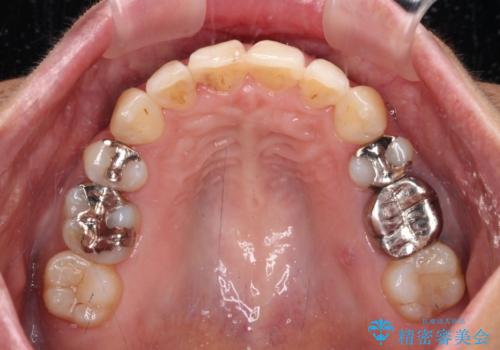

半年もしないうちに八重歯は解消し、治療も当初予定通り2年強で終えることができました。